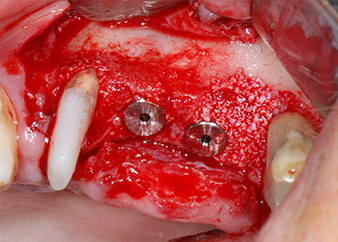

The implants (Restore, Keystone Dental, diameter 3,75 mm, length 8.0 mm) were placed with the implant motor

(Figs. 11 and 12).